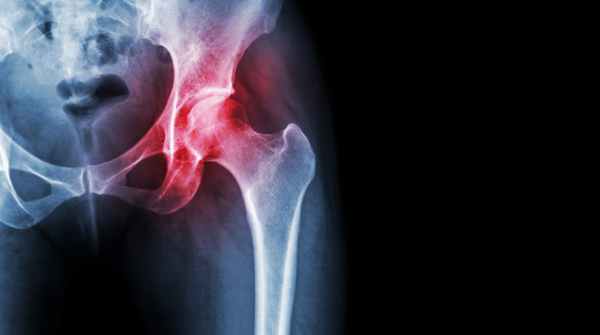

Коксартроз — деформирующий артроз тазобедренного сустава, заболевание являющееся лидером среди дегенеративно-дистрофических заболеваний опорно-двигательного аппарата, при котором первично поражается суставной хрящ и постепенно в процесс вовлекается костная ткань и окружающие мягкие ткани.

В начале болезни происходит изменения свойств суставной жидкости — в силу различных причин она становится вязкой и густой. А без должного «смазывания» суставной хрящ начинает подсыхать, а поверхность его становится шероховатой и покрывается трещинами.

В результате хрящ начинает истончаться, так как не выдерживает повышенного трения при движении. А расстояние между сочленяющимися костями сустава постепенно уменьшается. Кости как бы обнажаются из под хряща, давление на них увеличивается и они начинают деформироваться.

Артроз бедренного сустава – это прогрессирующее изнашивание и разрушение хрящевой ткани тазобедренного сустава. В результате человек испытывает сильную боль и ограничение подвижности в суставе. Это заболевание также известно как коксартроз или остеоартроз тазобедренного сустава.